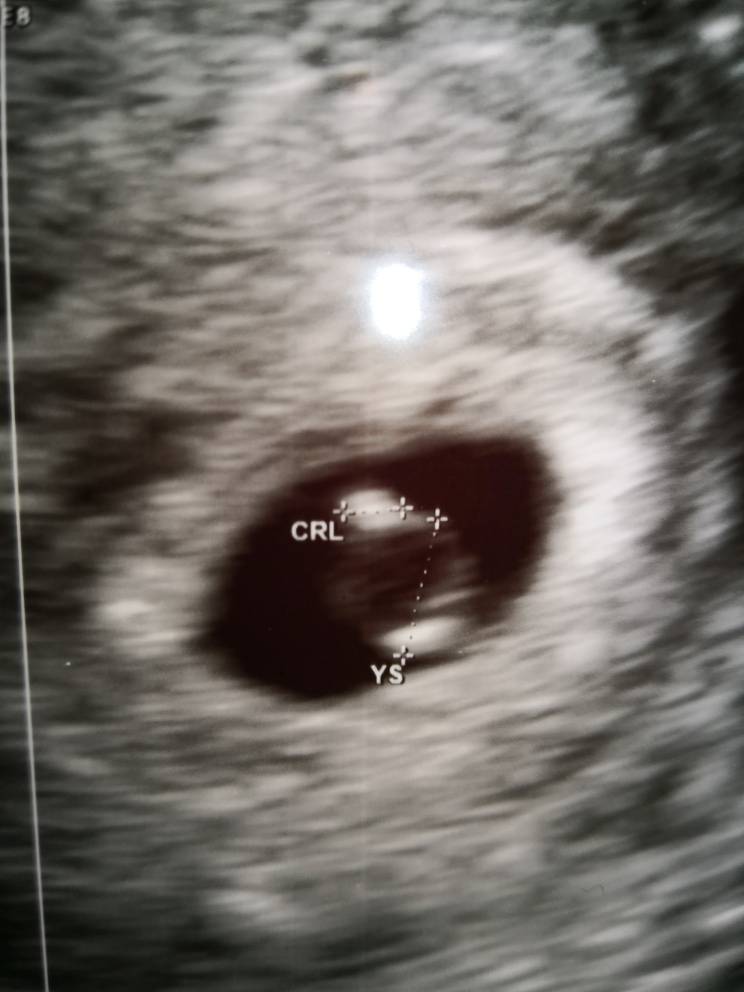

Zobacz załącznik 926960